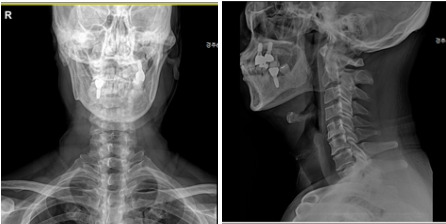

0613(1)_2.jpg 경추 MRI

경추부 MRI 검사상, C5-6-7-T1 협착증과 목디스크 소견을 보였습니다.